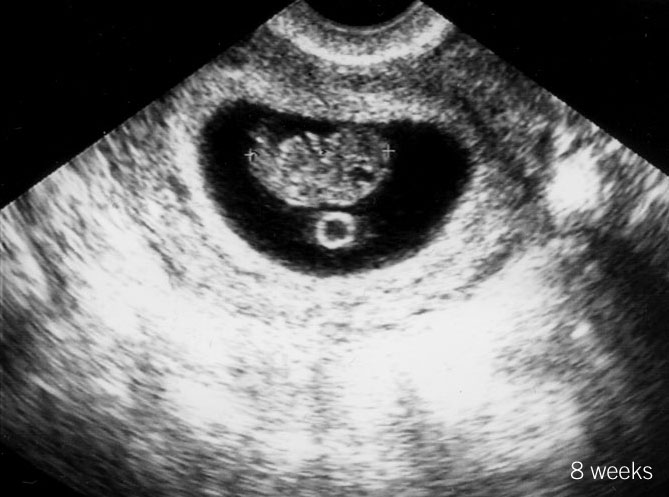

8 week sonogram